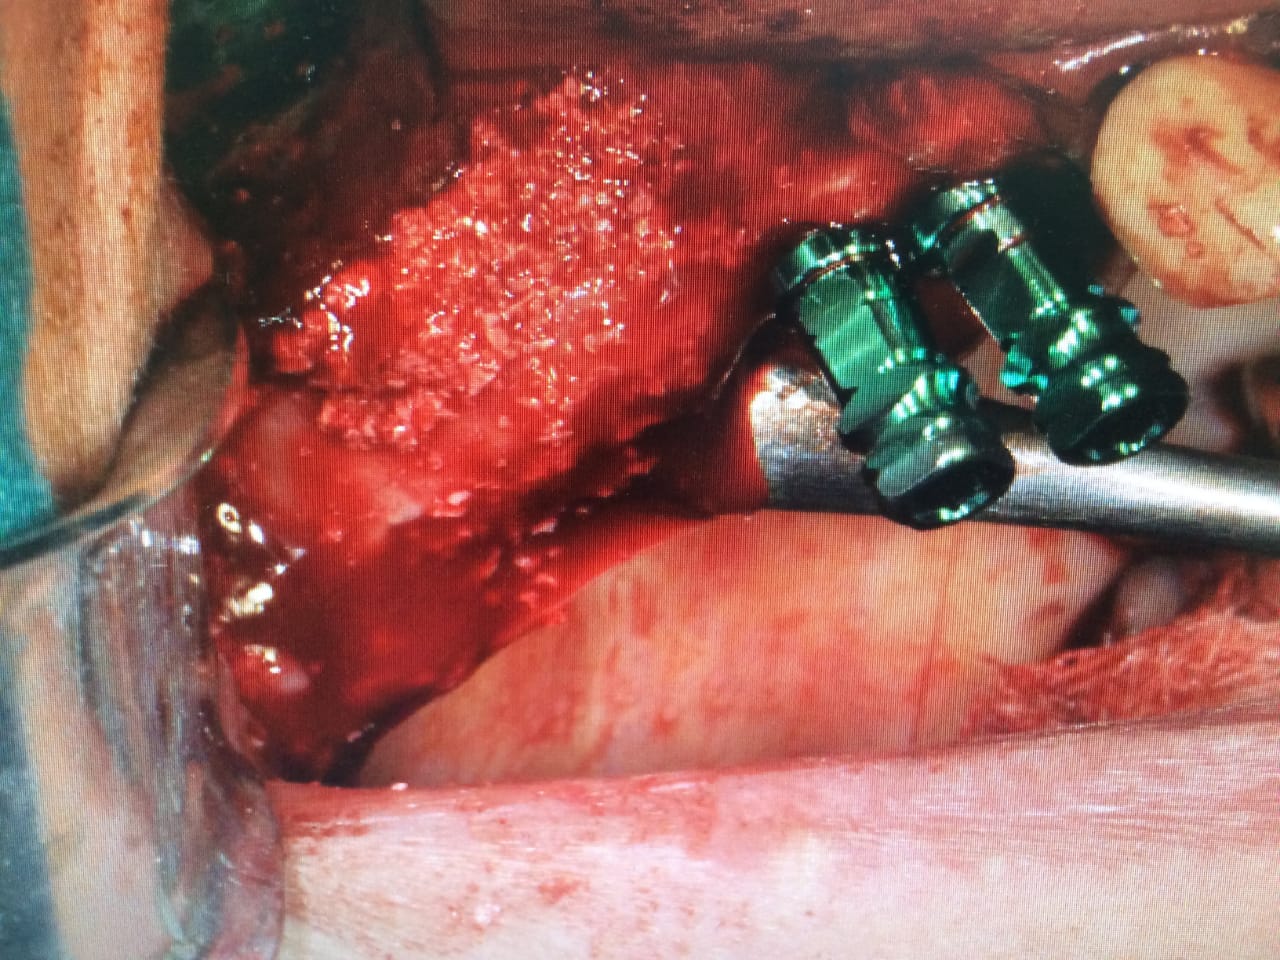

→ Pose du ou des implants

Durant cette étape, le praticien pose les implants dentaires pour remplacer les racines manquantes. À l’issue de cette intervention, vous sentirez des implants couverts par la gencive, et qu’ils sont mis en “nourrice” : cela permet à l’os de cicatriser autour des implants.

L’implant dentaire est placé dans la mâchoire sous anesthésie locale dans la majorité des cas, parfois sous anesthésie générale.

La chirurgie implantaire

Vidéo de la chirurgie implantaire